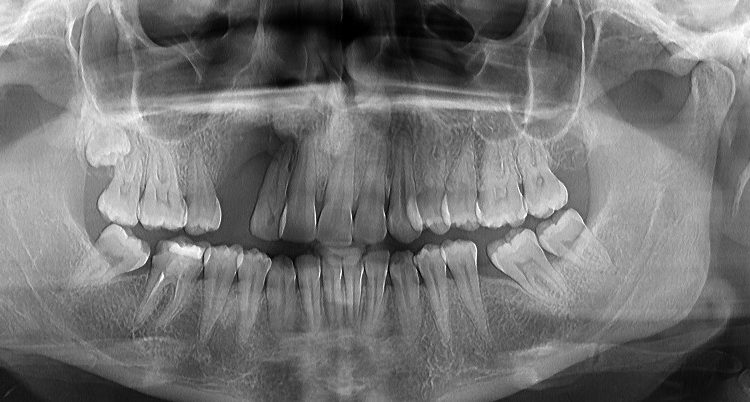

Pacienta in varsta de 39 de ani, a venit in clinica cu pierdere osoasa majora la maxilar in urma unei extractii de canin inclus si pierderea dintelui invecinat. Dupa o interventie de aditie osoasa, pacienta a primit  2 implante DENTIUM pe care s-a efectuat o protezare fizionomica fixa (baza titan plus suprastructura insurubata de zirconiu), cu refacerea conturului gingival si restaurarea functionala a arcadei. Pacientei i s-a propus si redresarea ortodontica pe care a amanat-o pentru o data ulterioara.